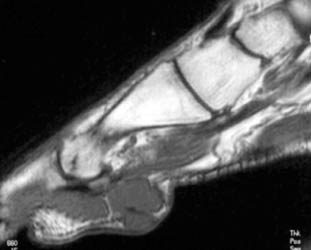

47 year old male with a 6 x 3.5 cm lobulated mass along plantar medial aspect of the 1st toe, which is hypointense on T1W and hyperintense On T2W images. Scattered small foci of hypointensity, representing calcifications is present on all the sequences. The soft tissue mass with small calcifications is also seen on the plain radiograph.